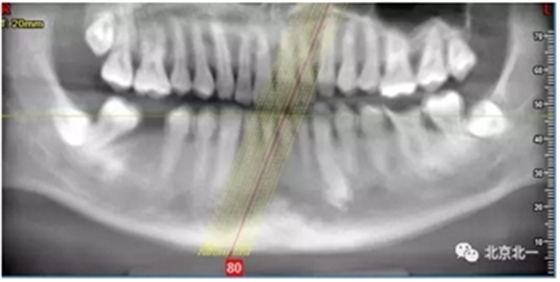

检查:46缺失, 47倾斜, 1度松动, 未见48萌出,

CBCT:骨量高度及宽度可, 48埋伏,低位阻生.37近中骨吸收

诊断:下颌牙列缺损, 48低位埋伏阻生 37 牙周炎